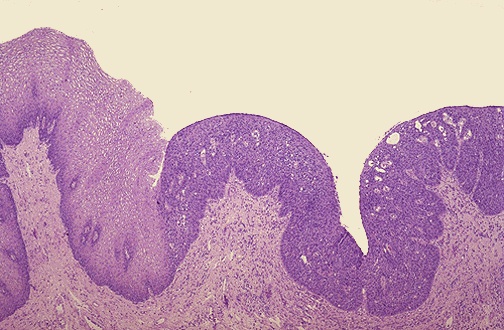

| This is the next step toward neoplasia. Here, there is normal cervical squamous epithelium at the left, but dysplastic squamous epithelium at the right. Dysplasia is a disorderly growth of epithelium, but still confined to the epithelium. Dysplasia is still reversible. |